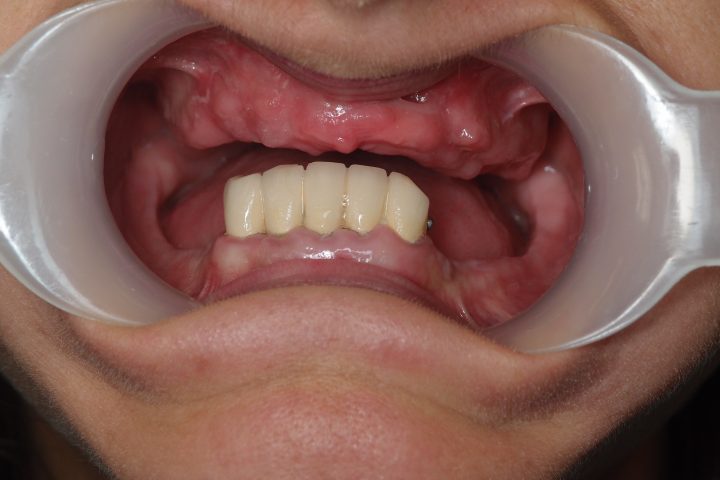

Zita ist eine schweizerische Patientin. Sie hat unserer Klinik im Jahr 2014 aufgesucht. Früher hatte sie oben Sanierung in Zürich, und hat eine Prothese in der Schweiz bekommen, die sie nie tragen konnte,

In Zürich hat Herr Dr. Szendrei eine CT-Aufnahme gemacht, und aufgrund von der Aufnahme einen Behandlungsplan erstellt.

Sie musste zweimal nach Budapest zu fahren. Beim ersten Besuch hat Herr Dr. Szendrei im Ablauf 5 Tagen die unten bewegenden Zähne entfernt, danach sowohl im Ober- als auch im Unterkiefer in der Frontregion 4-4 Stück Nobel Biocare Replace Implantate eingesetzt.

Natürlich wurde provisorische Prothese auch angefertigt.

Danach kam die 4 Monate lange Heilungszeit, zwischenzeit mussten die Implantate sich verknöchern. Danach war Zita 10 Tage lang in Budapest.

Im Ablauf 10 Tagen wurde eine sogenannte Stegprothese bearbeitet, die auf den Implantaten befestigt wurde, so sichert die ausgezeichnete Stabilität.

Beim Essen bewegt sich die Prothese auch nicht, hat keine Gaumenplatte, und braucht man dazu keinen Klebstoff.